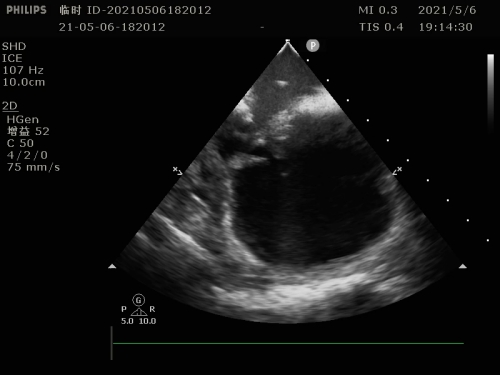

为防止术中出现卒中的可能,同时需术前评估左心耳及左心房的情况,必须搞清楚房颤患者心房是否出现血栓,食道超声检查显得十分必要。可该患者却无法耐受食道超声。刘燕锋向患者及家属建议,只能选择在术中使用超声导管,通过超声导管,一可以检查病人左心耳及左心房有无血栓;二可以指导房间隔的穿刺,由于右位心患者与正常人不同,使用超声导管协助手术可以降低手术难度,保证手术安全;三是术中可以实时监测心包有无积液。

术中超声检查左心耳